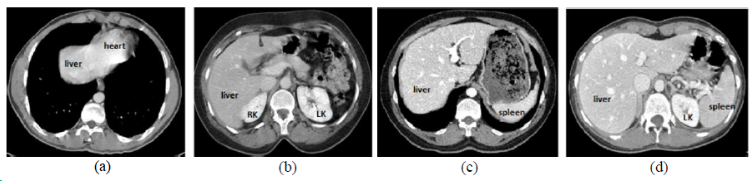

## CHAOS

| [CHAOS](https://chaos.grand-challenge.org/) | 肝/肾/脾 | 分割 | CT+MRI | 40CT+120MRI | 0/1标签 | dcm |

CHAOS是一个多脏器,多模态分割数据集。

[Aistudio下载](https://aistudio.baidu.com/aistudio/datasetdetail/23864)